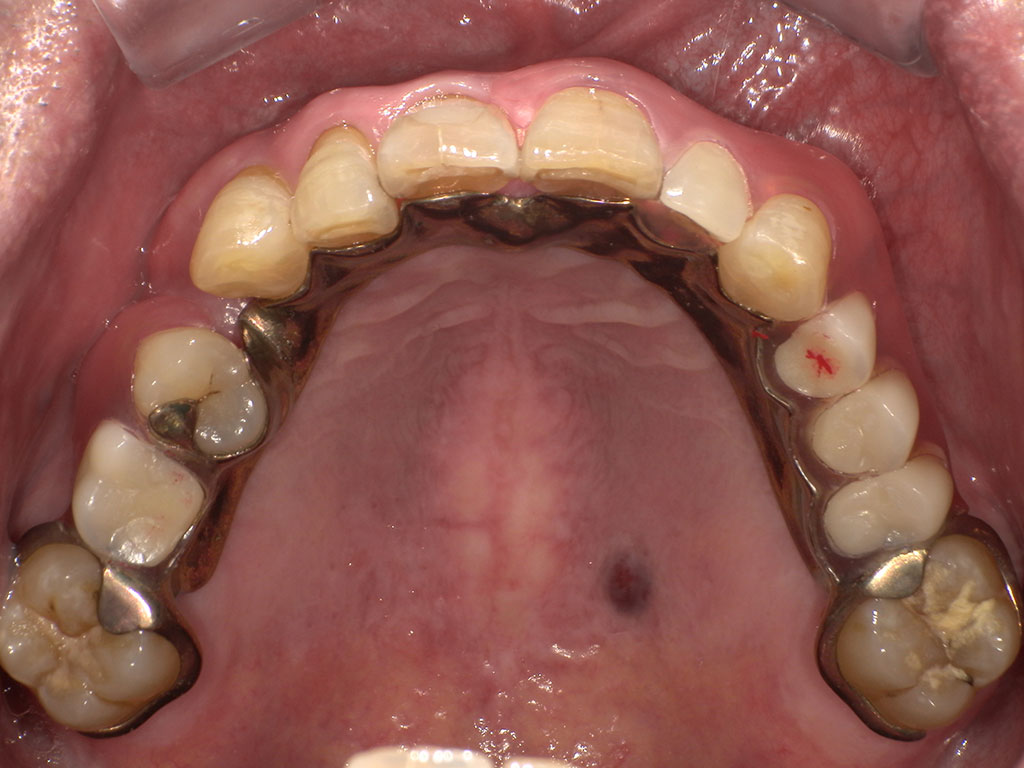

After1

After2

上顎右6番左2456番の欠損を補うスマイルデンチャー(Sing)

金属部分がない、フィット感がある、入れ歯を支える歯への負担を軽減させるため、上顎右6番左2456番の欠損を補うスマイルデンチャーを作成